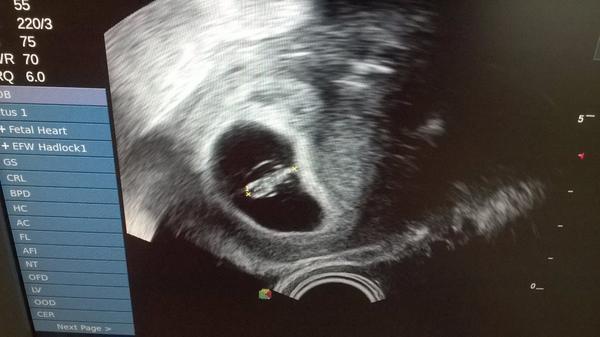

holky co znamená živá gravidita?že je srdíčko?

Ahoj holky 🙂. Dneska sme byly na kontrole, všechno v pořádku, už sme dostaly i průkazku a máme se dopředu objednat na screening 🙂. Podle utz sme 7+4 🙂